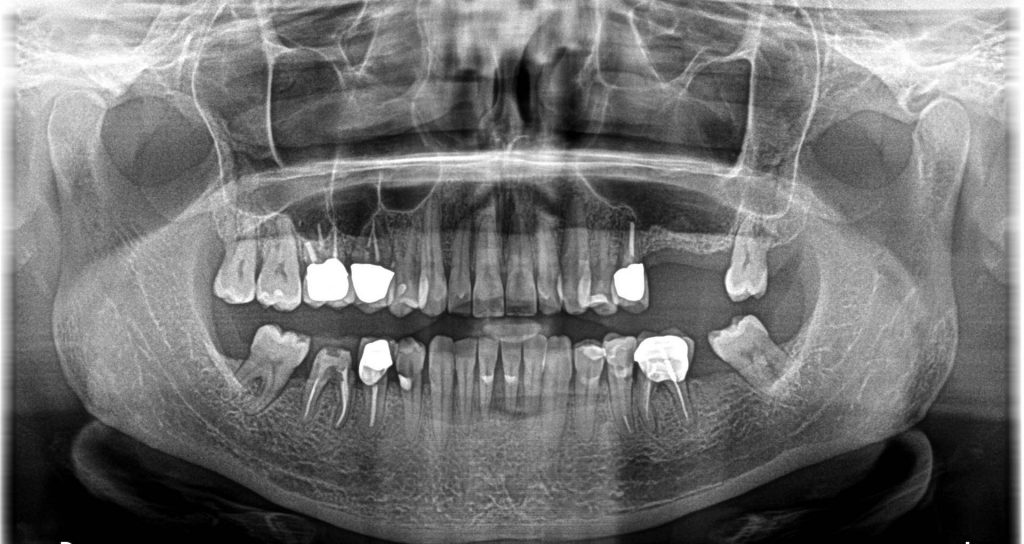

Panoramix Xray

panoramic view pre-op